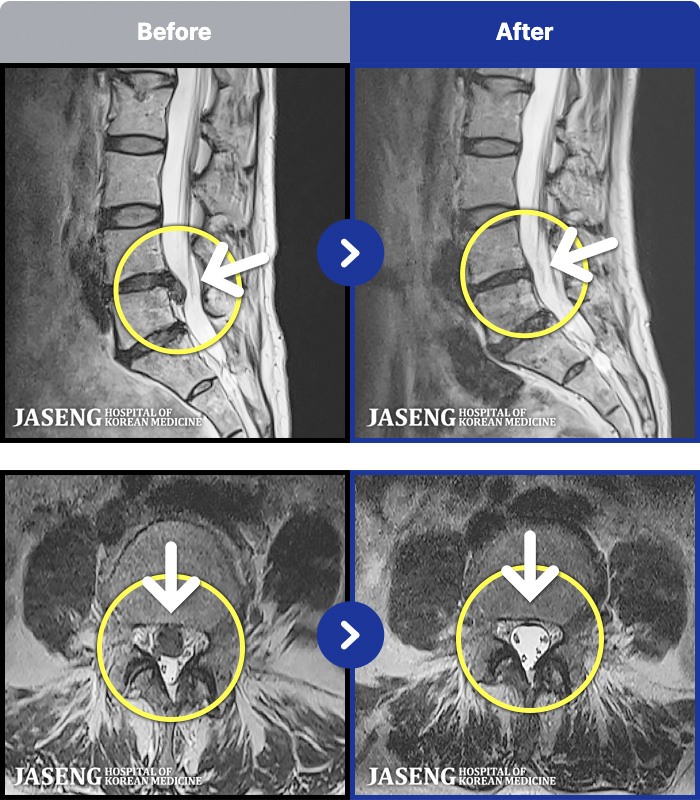

MRI ġ

1,240 MRI ũ ʸ Ȯϼ.